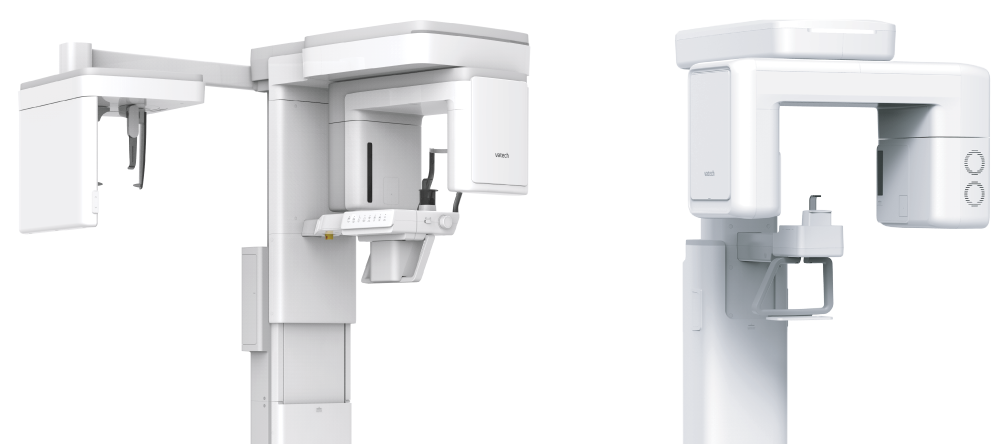

THE ADVANCED IMAGING SOLUTION

FOR ACCURATE DENTAL DIAGNISIS

FOR ACCURATE DENTAL DIAGNISIS

INTEGRAL FOV FOR 3D IMAGE

The Vatech A9 offers precise, high-quality panoramic images, enhancing diagnostic accuracy and treatment planning. Its innovative FOV provides a wider view of the dentition, reducing the risk of cutting out images of teeth. The 8×8 images enable comprehensive diagnoses and treatment planning, including complex implant surgeries and TMJ diagnoses, in a single scan.

THE ADVANCED IMAGING SOLUTION

FOR ACCURATE DENTAL DIAGNISIS

FOR ACCURATE DENTAL DIAGNISIS

INTEGRAL FOV FOR 3D IMAGE

The Vatech A9 offers precise, high-quality panoramic images, enhancing diagnostic accuracy and treatment planning. Its innovative FOV provides a wider view of the dentition, reducing the risk of cutting out images of teeth. The 8×8 images enable comprehensive diagnoses and treatment planning, including complex implant surgeries and TMJ diagnoses, in a single scan.